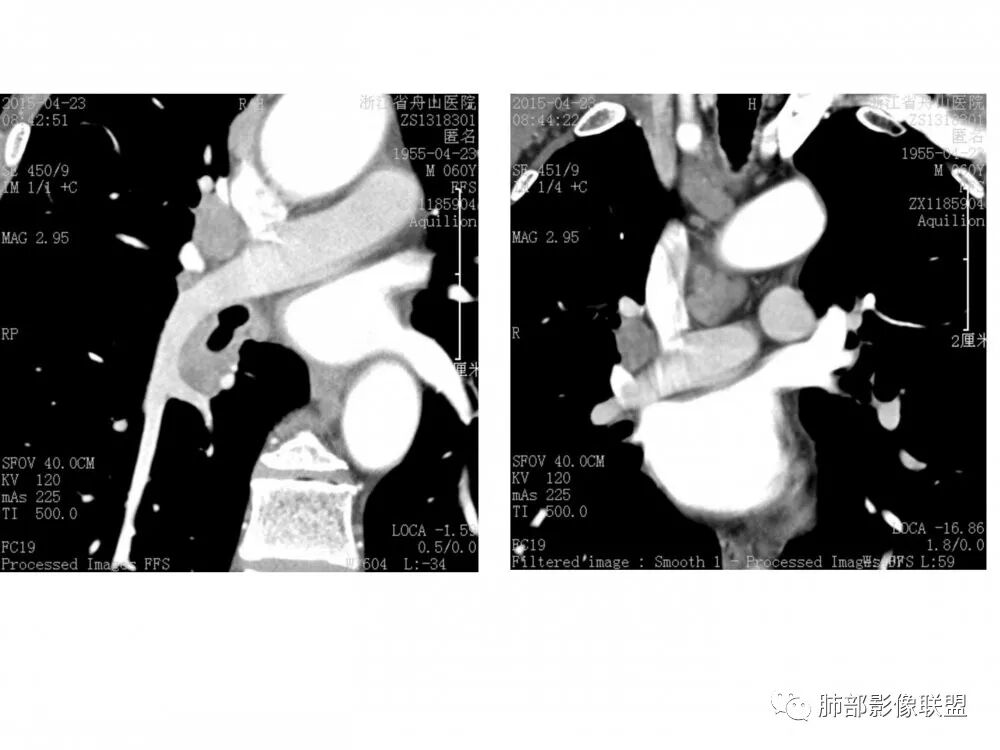

右肺下叶支气管不规则软组织肿块,病灶沿支气管生长,有一定的张力,部分包绕支气管壁,增强病灶内可见中度强化,内部有延迟强化的特点,周围淋巴结增大,诊断恶性病变无疑,远端无明显支气管阻塞,主要考虑粘液表皮癌,腺样囊腺癌,鳞癌之间鉴别,病灶有类似神经源性病变生长方式,腺样囊腺癌,其次考虑鳞癌或粘液表皮癌。

右肺门结节,内见包埋血管,不均匀强化,长轴沿支气管且围绕支气管生长,支气管受压狭窄而未阻塞,肺门及纵隔见肿大淋巴结,老年男性,似有肺气肿背景,考虑恶性肿瘤性病变,首选小细胞肺癌

右肺下叶支气管开口新生物,轴位管腔及纵向基底干大部分受累狭窄,支气管管壁破坏并突破形成腔外肿块,血管累及变细,肉眼观轻度强化,右肺门、纵膈淋巴结肿大,恶性没问题,阻塞性炎症不明显,类癌强化明显不支持,老年男性,首先考虑小细胞癌,鉴别不典型鳞癌和腺癌。

自信人生

右肺下叶开口支气管内新生物,破坏管壁向腔外膨胀生长,累及各基底段开口,无明显坏死,有局部强化,远端无明显阻塞,右肺门及纵隔淋巴结肿大,考虑恶性肿瘤。大气道肿瘤不支持腺癌。小细胞癌大多为周围病灶引起肺门、纵隔淋巴结转移,肺门淋巴结明显肿大后侵犯支气管粘膜到达支气管内(从外到内),本例病灶从管腔内向腔外长,不支持小细胞癌。病灶为轻→中度强化,类癌显著强化为主→不支持,鳞癌、腺样囊性癌一般中度强化,鳞癌大多有阻塞性病变,本例无明显阻塞不支持鳞癌。粘液表皮样癌一般为轻度不均匀强化。感觉病灶为轻中度不均匀强化。综上首先考虑粘表,其次腺样囊性癌。待支气管镜活检明确。

病理结果:鳞癌